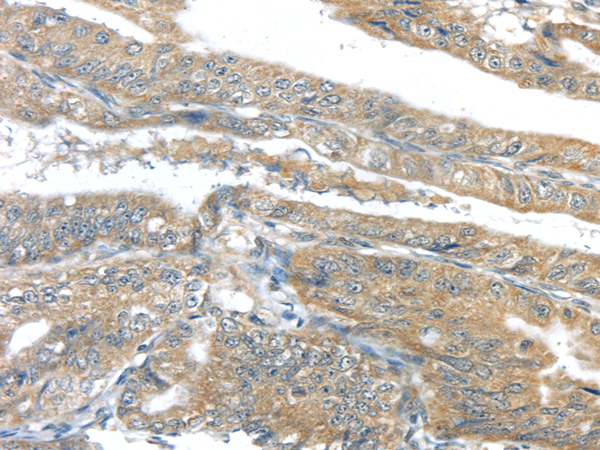

Product information "Anti-AKT2"

| Application: | IHC, ELISA |